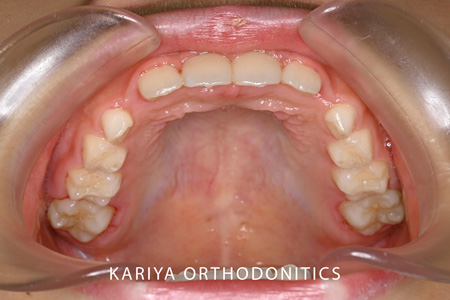

After

3本の前歯が反対咬合になっている歯並びの1期治療を行いました。

本症例では、リンガルアーチと補助断線により上顎前歯の唇側傾斜と下顎前歯の舌側傾斜を行いました。